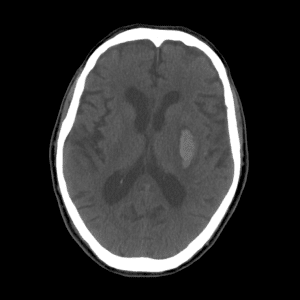

PICA infarct

Case #4